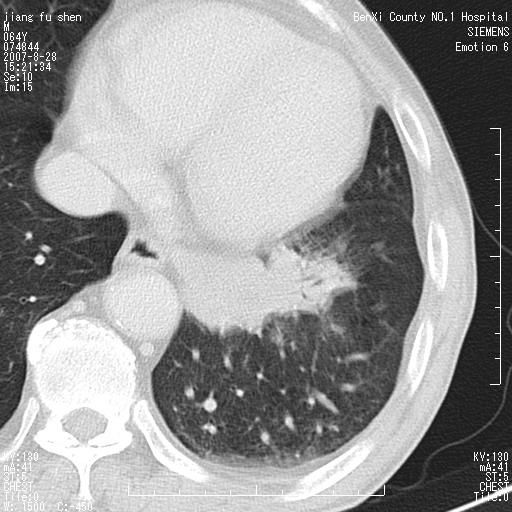

男、64、咳嗽、发烧一周、左肺呼吸音稍弱。既往肺结核,右手结核。

本次扫描患者未带原片,左肺下叶发现病灶。左肺上叶空洞,5组淋巴结肿大,1cm左右。

平扫20-33hu

增强31-33hu

1分半44-52

2分55-67

左肺下叶前内基底段支气管明显偏心性狭窄,周围分叶状肿块,伴有阻塞性肺炎,支持肺癌可能性大。